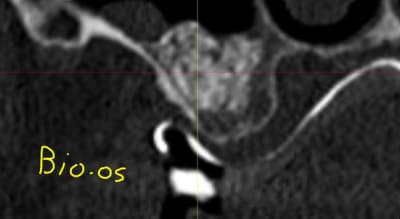

je ne fait pas durer le suspens sur la qualité des biomatériaux utilisée;

à droite : BIO-OS

- grosses particules

- beaucoup de publications

- bouillies infâme lors de l'ouverture

- pas de résorption

- beaucoup de particules encapsulées

- c'est pas de l'os

- lutte contre la pneumatisation sinusienne